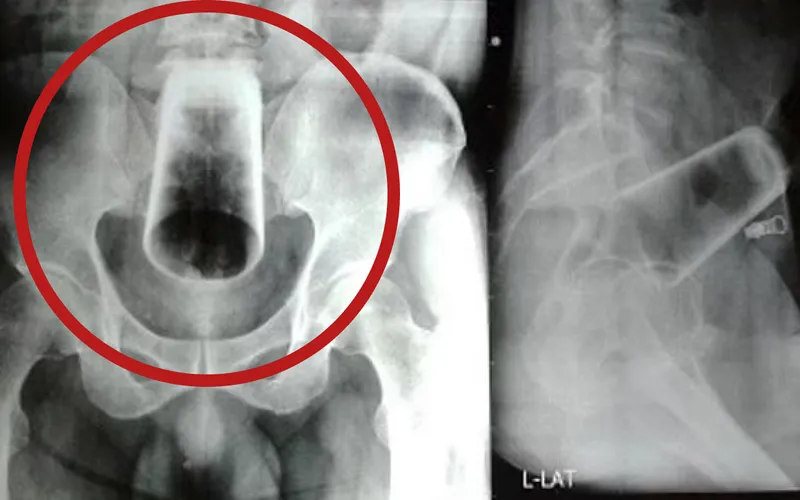

A încercat să scoată singur paharul, dar încercările sale au eșuat la fel ca și cele ale medicilor care, după ce i-au făcut o radiografie tipului, nu au reușit să prindă paharul care se deplasase în abdomenul său.

Foto: Nepal Medical Association